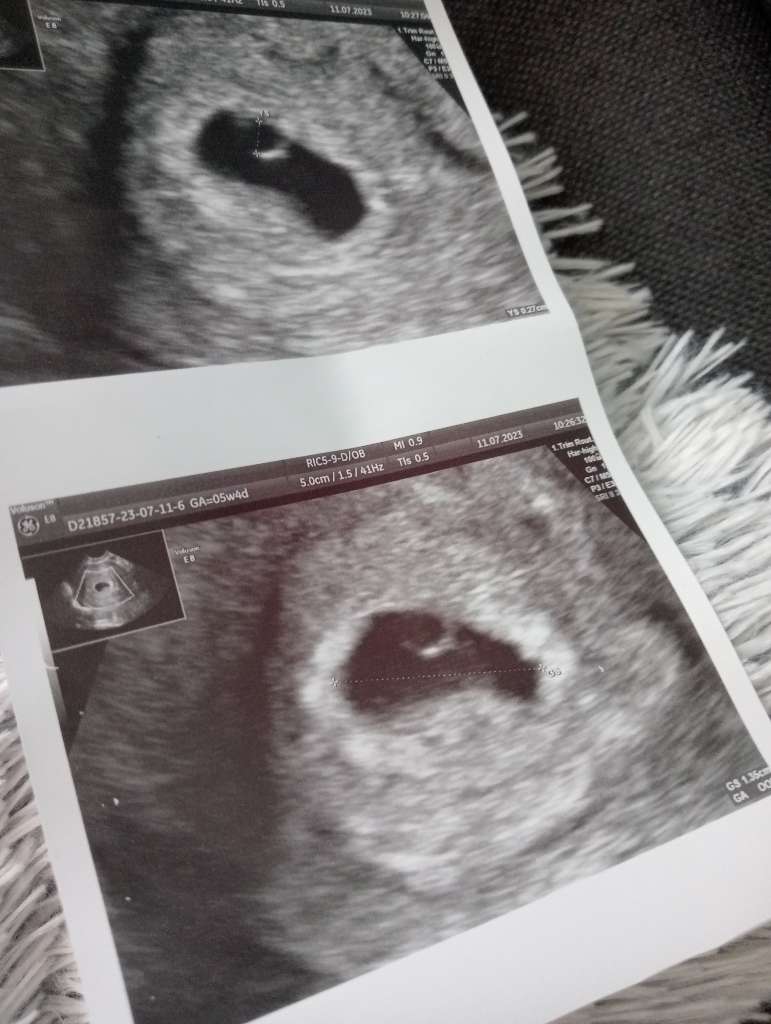

Ja już po wizycie ☺️

Wszystko dobrze słuchajcie, wyniki badań mam dobre ( przepisane mam kolejne ) a na USG było widać YS 💚 za tydzień już powinno być serduszko 🫣